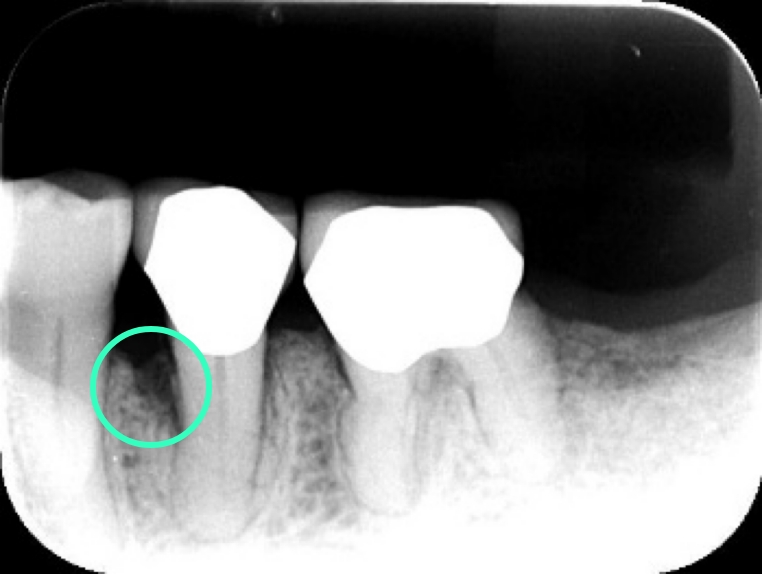

特に噛み合わせの変化は、歯根破折(歯の根が竹を割ったように割れてしまうこと)と歯を支えている歯槽骨の垂直的な吸収を引き起こしますが、噛み合わせの変化は緩やかに進行するため、自覚症状はほとんどありません。さらにこの特異な咬合状態が続くと、歯周病菌の影響で歯槽骨の垂直性吸収が起こり、破壊された骨は膿となって歯肉の中に溜まっていきます。その結果、歯肉が急に腫れ、噛むと痛みが出てくる (咬合痛)事態へと発展していきます。レントゲンでは歯槽骨の吸収が顕著に見えます。(レントゲン写真参照)

このような場合、歯周ポケットは5mm以上になってしまうことが多く、従来は歯肉を切り開いて患部の清掃をするフラッペ手術(歯周外科手術)を選択するのが常識でした。しかし、歯肉に外科的侵襲が加えられることになるので、創傷治癒には一定の時間がかかるというデメリットがあります。